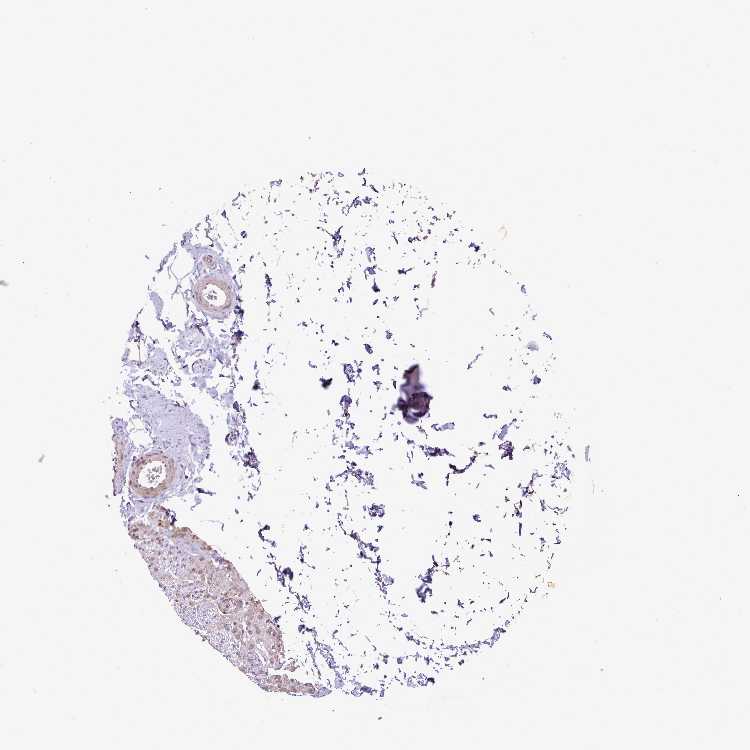

SOFT TISSUE 1 - Antibody stainingi

Antibody staining in the annotated cell types in the current human tissue is reported as not detected, low, medium, or high, based on conventional immunohistochemistry profiling in selected tissues. This score is based on the combination of the staining intensity and fraction of stained cells.

Each image is clickable and will lead to virtual microscopy that enables deeper exploration of all samples and also displays staining intensity scores, fraction scores and subcellular localization as well as patient and tissue information for each sample.

Antibody HPA051413

Chondrocytes Medium

Fibroblasts Medium

Peripheral nerve Low